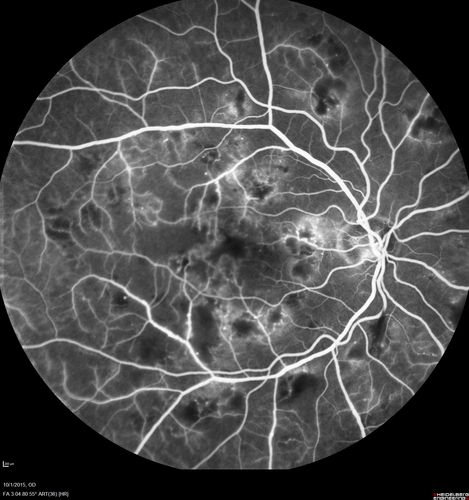

Hairy Cell Leukemia - Retinal Hemorrhage and twig Branch Vein Occlusion

79 year old man He has had hairy cell leukemia since 2002.  He is in remission.  His last blood tests were 9/2018.  He just moved down here and needs a new leukemia doctor.  His vision is fine.

VA OD: Dcc20/25

VA OS: Dcc20/25

IOP: TP: OD:12 OS:12